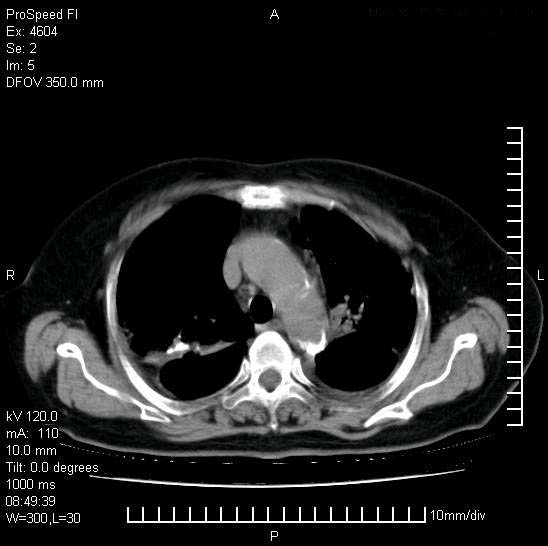

标题: CT15528:女性,79岁,近几日晚上高热,39度,仍咳少量血 [打印本页]

十几年前曾患肺结核,一周前突咳血约100ml,中性粒细胞稍高,诊断两上肺陈旧结核,下肺炎症,给予抗炎治疗,近几日晚上高热,39度,仍咳少量血,4天前ct及今天ct上传。

今天ct

支持陈旧性肺结核并两下肺感染,两侧胸腔积液。

短短几天内,病变范围明显增多扩大,以左侧明显,而且双侧出现胸水,还是考虑感染.

短短几天内,病变范围明显增多扩大,以左侧明显,而且双侧出现胸水,我更多考虑左侧中心性肺癌并并阻塞性不张及肺炎,炎症变化也太快了!

1)两肺结核并感染。2)不排除左肺上叶中央型肺癌并阻塞性肺炎、肺不张可能;建议行纤支镜检查。3)右肺门及纵隔淋巴结肿大。4)双侧胸腔积液。

陈旧性肺结核及左下肺不张,咯血后肺部感染,双胸腔积液,高热可能与痰液引流不畅有关。